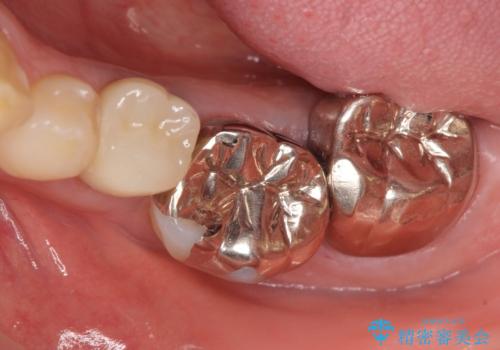

- 左下の奥歯がズキズキ痛むので診て欲しいといらっしゃった方の症例です。他院では5番目と7番目の歯を抜歯してインプラントと言われたが、出来れば歯を残したいとのことでした。

痛みの原因は6番目の虫歯であること、5番目、6番目の歯は歯茎より深い虫歯であり現状では保存が難しいことを説明した上で、歯を挺出させる部分矯正と歯茎を下げる歯周外科を行いました。